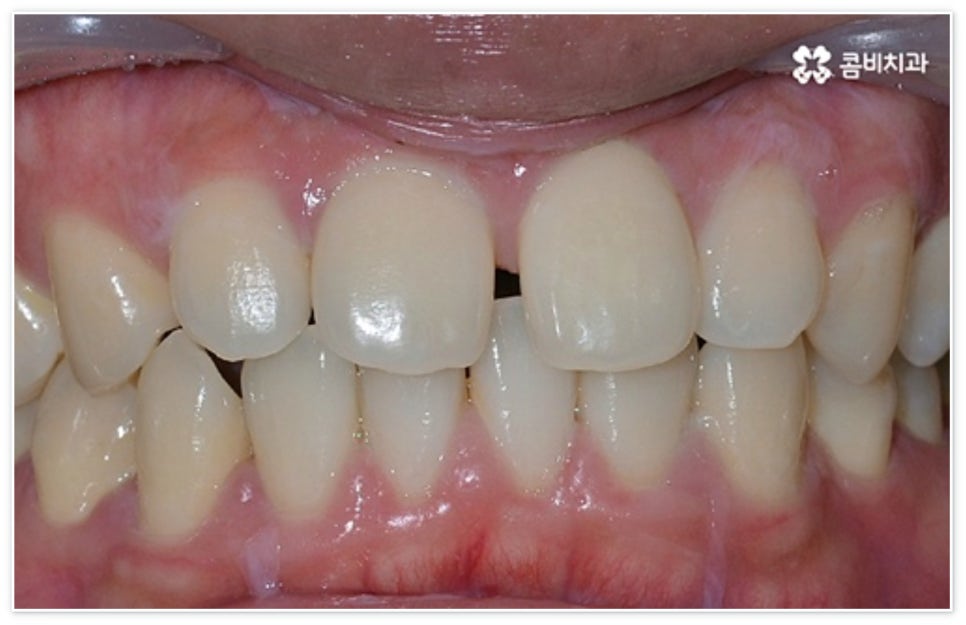

앞니 벌어짐 은 생각보다 많은 사람들이 흔하게 겪는 치아 문제 중 하나로, 언뜻 즉각적인 치료가 필요한 심각한 질환은 아니라고 생각할 수 있으나 앞니 틈으로 구강 내부가 어둡게 드러나 보이면 미관상 좋지 않을 뿐만 아니라 발음이 새거나 저작 기능에 문제가 생기는 등 일상 속 여러 불편함을 가져올 수 있습니다. 또한 음식물 찌꺼기가 끼기 쉽기 때문에 구취가 나거나 구강 질환을 초래할 가능성도 높으므로 치료를 통해 개선해 줄 필요가 있어요.

보통 치열을 가지런하게 바꾸고자 할 때 대표적으로 교정 치료를 고려하지만 비교적 오래 걸리는 시간이나 비용적인 부담 등 여러 가지 이유로 망설이는 분들도 있을 수 있는데요. 이때 앞니가 벌어진 정도가 심각하지 않고 치아 사이가 벌어진 원인을 살펴봤을 때 교합이나 구조적인 부분에 문제가 없다면 치아 전체를 이동시키는 교정 치료 대신 빈 공간을 채워주는 치료를 통해 수복이 가능할 수 있으니 먼저 환자분들께서 자신의 상황이 어떠한지 꼼꼼하게 검진을 받아보고 상담을 진행해 적합한 방법을 찾아보시길 권유드리고 있습니다.

환자분들에 따라 다르지만 통상적으로 전체 교정이 1년에서 2년 반 정도 소요된다면 부분 교정은 6~8개월 정도로 기간 단축이 가능하여 치료에 대한 부담을 줄일 수 있으며 대부분 발치 과정 없이 필요한 부위에만 브라켓을 부착하는 만큼 불편함이 적고 구강 관리도 용이한 편이니 (사진에서 살펴볼 수 있는 케이스) 이에 대해서 자세히 알아보시면 좋을 거예요. 물론 누구나 가능한 것은 아니고 개인의 구강 상태에 따라 진행을 해야 하므로 꼼꼼한 검진과 충분한 상담부터 받아보시길 권유드리고 있습니다.